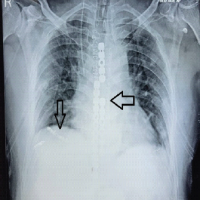

The plates were initially secured with cortical screws, followed by locking screws bicortically, while ensuring that drilling was performed cautiously and checked under thoracoscopy to avoid irritation of underlying structure (Vid). Final reduction was deemed satisfactory and confirmed through fluoroscopy and thoracoscopy. The wound was closed in layers and stapled. The post-operative period was uneventful, and the patient was able to sit upright the following day. Sutures were removed on 12th postoperative day, and follow-up X-rays (Fig. 6) showed that the implants were in good position.

Figure 6: Final check xray and 1yr follow up x ray.